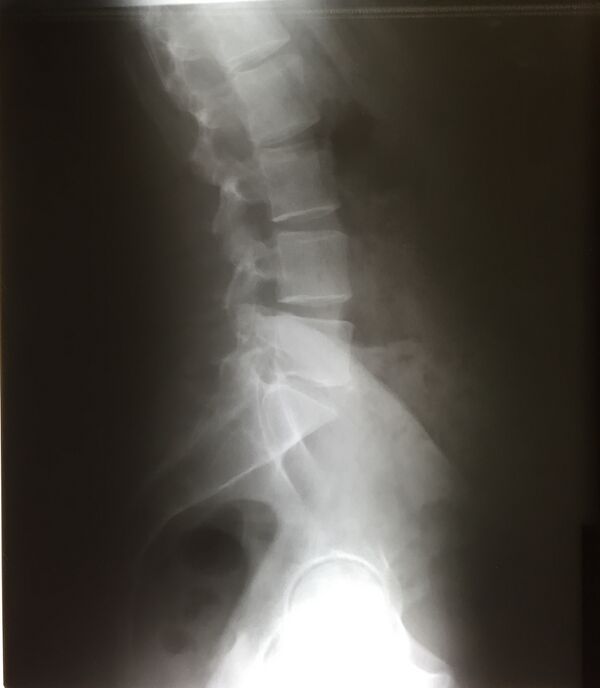

Есть 2 вида изгиба позвоночника: лордоз и кифоз. Лордоз — это те части позвоночника, которые выгнуты вентрально (вперед) — шейный и поясничный. Кифоз — это те части позвоночника, которые выгнуты дорсально (назад) — грудной и крестцовый.